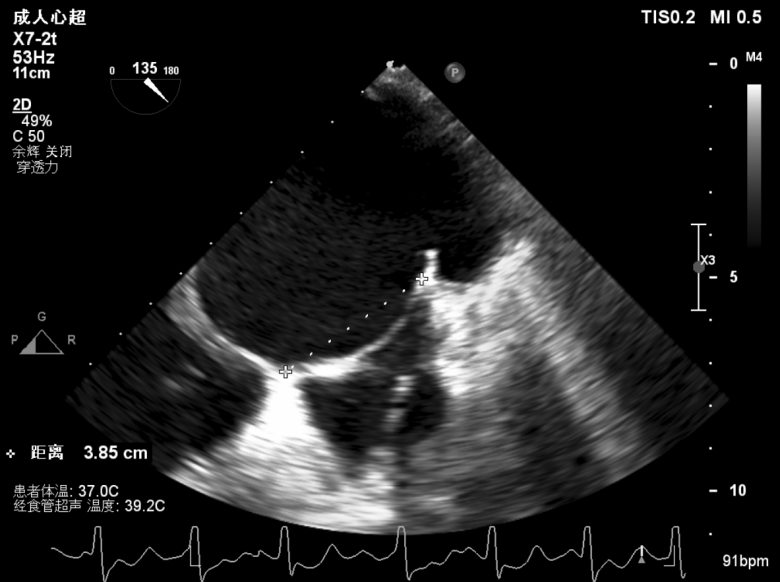

团队在反流最严重的2区精准植入1枚二尖瓣夹,即刻反流下降至微量,血压即刻上升20mmHg,跨瓣压差不升反降,由3mmHg降至2mmHg,改善效果明显,手术仅耗时一个半小时。 这是时隔四年继2020年指导开展区域内首例TAVR(经导管主动脉瓣置换)手术之后,陈茂教授再次带领华西团队,指导开展内自同城区域首例TEER术。陈茂教授对四院心内科心超图像的采集、房间隔穿刺的技巧、手术流程细节的把握、团队的默契配合、术前术后的管理表示称赞,鼓励四院心内科再接再厉造福区域患者。 患者为71岁老年女性,反复出现心累、气促已经超过10年,10多年来心衰的症状逐渐加重,间隔时间越来越短,且近1个月来已经3次因心衰住院,本次住院前已经无法耐受缓慢步行、如厕等日常生活,BNP超过了3000ng/ml。心电图为房颤,心超示左心室明显增大(65mm),重度二尖瓣反流(4+,CarpentierI+IIIb型),射血分数仅为31%。前叶长度:2.27cm且瓣尖增厚,后叶长度:1.14cm且局部钙化,瓣口面积:4.08cm2,反流宽度:1.7cm。患者及家属均拒绝外科开胸手术。 难点: 1.食道超声下该患者房间隔较厚较韧,且粗测高度仅为4.0cm,对穿刺的位置和技巧有较高要求; 2.左心扩大,反流宽度约17mm,放一个夹子可能不能有效解决反流,如放两个夹子需side by side 平行放置,但放置两个夹子有术后狭窄的风险; 3.前后叶对合似有间隙,若选用长宽夹子,会增加瓣叶张力,有瓣叶撕裂的风险,若选用短宽夹子,其捕获瓣叶的难度将增加; 4.患者心功能极差,手术需稳、准、快,不能耐受任何并发症风险。 影像资料 房间隔穿刺